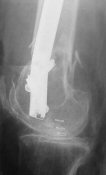

A new toy is more interesting and fashionable. And anyway it is not panacea, i have already seen presentations with LISS failures like the attached one presented by D.Seligson. And people also demonstrated incisions say that the method is not so LESS invasive as it supposed to be.